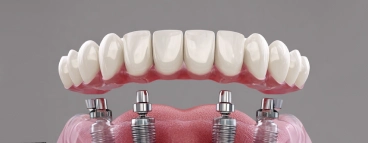

Стоматологическое отделение поликлиники состоит из терапевтической, хирургической, ортопедической служб и технической лаборатории, располагается на 5 этаже поликлиники в Петроградском районе.

Врачи терапевтической службы отделения в своей работе используют все новейшие методы лечения зубов и применяют все виды пломбировочных материалов. В современной стоматологической практике используются разнообразные пломбировочные материалы, позволяющие расширить показания к их применению и повысить эффективность пломбирования, и различные методы реставрации зубов.

Цель любого стоматологического лечения заключается в обеспечении функционального и здорового состояния зубов. Для успешного лечения определенное значение имеет качество пломбирования каналов.

В стоматологической поликлинике Петроградского района каждое рабочее место стоматолога врача терапевта оснащено необходимым оборудованием – апекслакатор; эндодонтические наконечники; материалы, способные обеспечить герметичность обтурации корневых каналов. Врачи широко применяют новые методы неинвазивного лечения хронических периодонтитов.

Контроль и анализ проведенных методов показали реальные сроки восстановления костной ткани в патологических околоверхушечных очагах деструкции. Стоматологи терапевты проявляют искренний интерес к пациенту и состоянию его здоровья: при диагностике делаются необходимые рентгенограммы, проводят тщательное стоматологическое обследование, помогают в постановке правильного диагноза. Регулярные контрольные осмотры позволяют своевременно выявлять проблемы. Результаты высококачественного стоматологического лечения сохраняются в течение продолжительного времени.